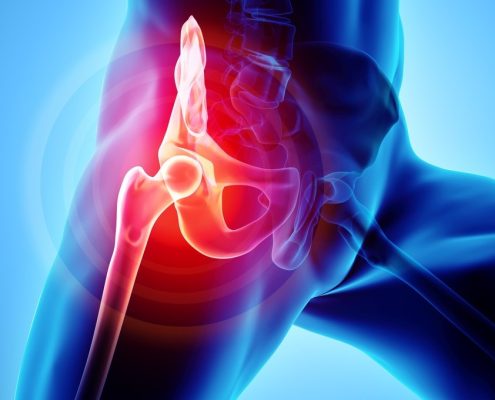

The Adult Hip patient

Day One - Differential Diagnosis & Manual TherapyDay Two…